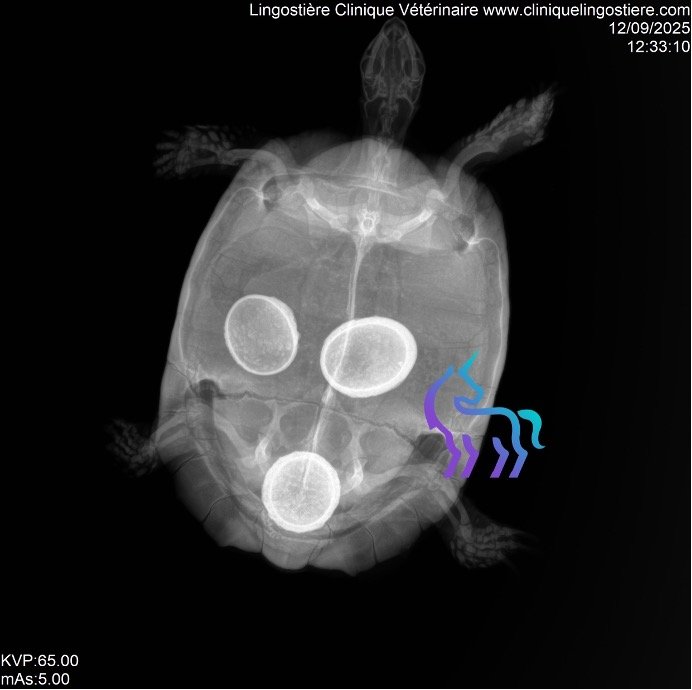

Rétention d’œufs chez la tortue (Dystocie) : causes et traitements

La rétention d’œufs post-ovulatoire est une pathologie fréquente chez les femelles tortues en captivité. Bien que son diagnostic soit rapide via imagerie, il est impératif d’identifier les causes profondes pour garantir la survie de l’animal.

Traitement chirurgical : la plastrotomie

En cas d’échec du traitement médical ou si la tortue présente des signes de septicémie ou d’obstruction, l’intervention chirurgicale devient vitale : l’Ovario-salpingectomie par plastrotomie.